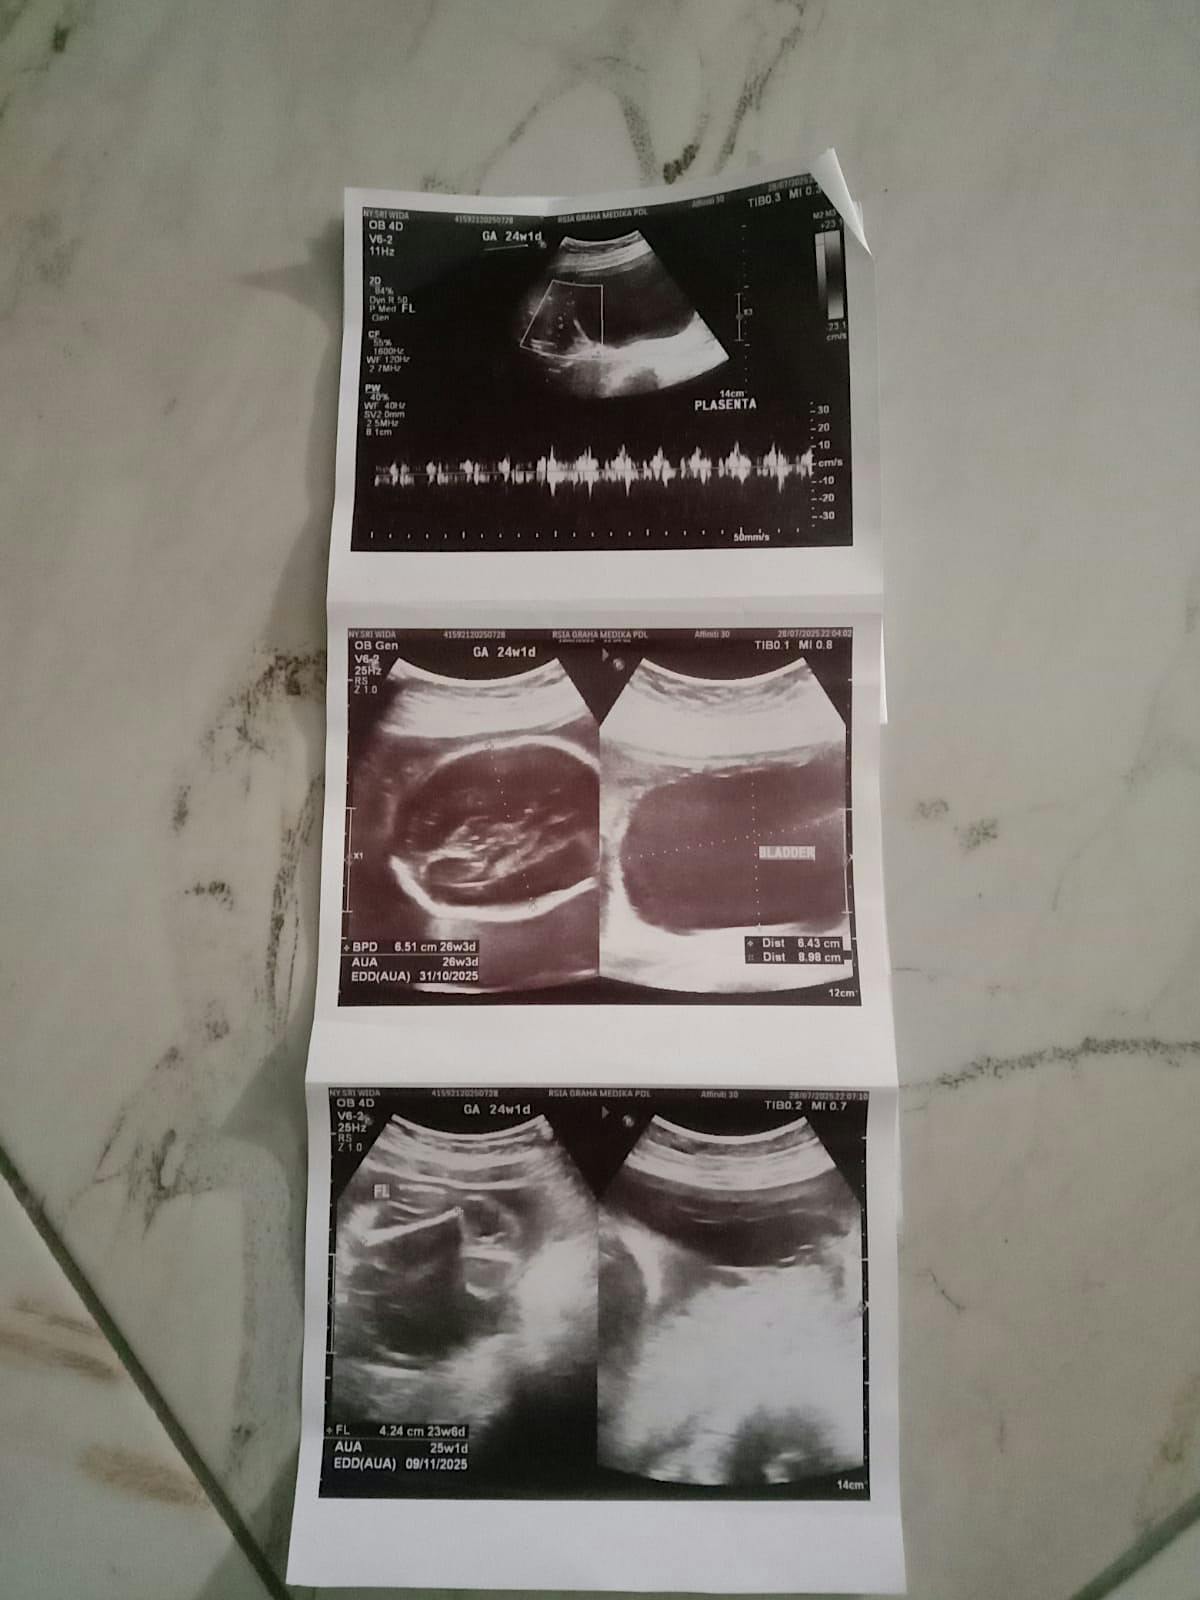

Sri kini mengandung. Bahagia bercampur cemas, karena dokter berkata janinnya mengalami kelainan saluran kencing. Malam-malam Sri dipenuhi tangisan. “Bagaimana kalau tubuh anakku tak sempurna?”

Saat lahir bayi uwessri harus lahir menggunakan metode caesar karena dokter menyatakan ibu sri tak bisa melahirkan anaknya dengan normal dikarenakan kondisi tubuhnya yang memiliki keterbatasan sehingga tak bisa melahirkan anaknya dengan normal. Saat melahirkan sri dan bayi selamat namun keadaan bayi yang harus di pisahkan di ruang NICU karena bayi mengidap Hisprung disasae (tak memiliki lubang anus) akhirnya bayi langsung di tidak operasi atas persetujuan uwes dan sri karena mau gimana lagi uwes dan sri hanya bisa berdoa akan putra kelahiranya. Sangat dilematis disaat ibu sri dibolehkan pulang dari rumah sakit namun Bayi uwes dan sri harus tetap di rumah sakit karena kondisinya kritis paska operasi pembuatan lubang anus di perut. Bayi uwes dan sri hanya bertahan 1 minggu dan tak bisa di tolong oleh tim Rumah sakit dan meninggal di rumah sakit.